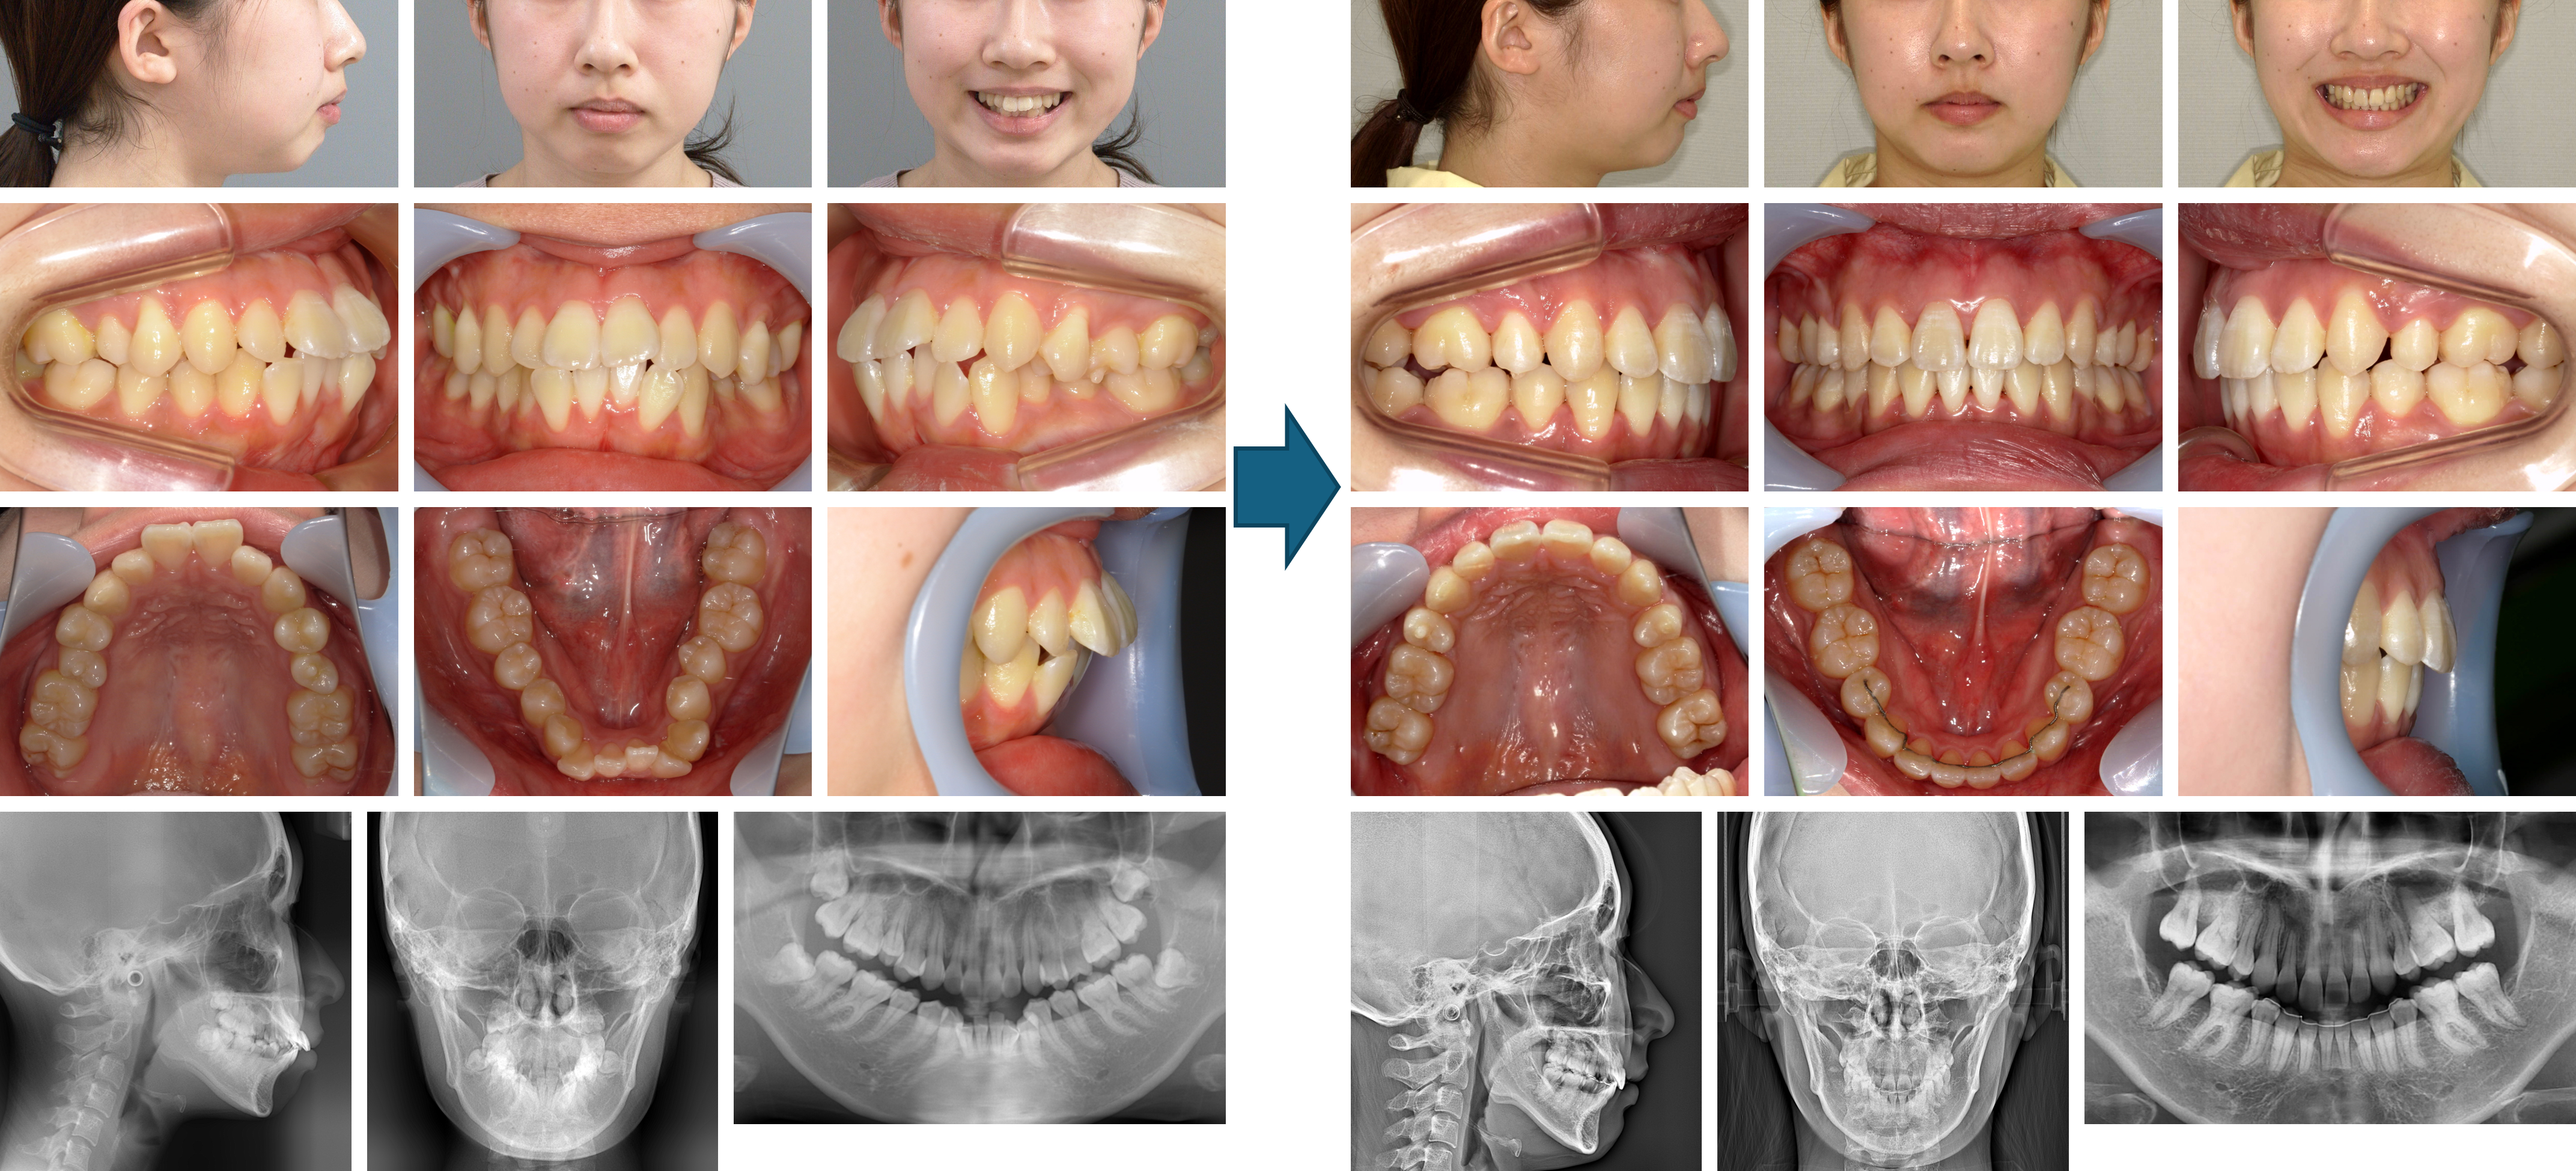

【治療例】初診時年齢:22歳4か月 / 性別:女性 / 主訴:前歯が出ている。もっと笑顔が作れるようになりたい。

症例の概要:この症例は左側上顎中切歯の突出による口唇閉鎖不全を主訴に来院された。上顎の歯列弓はV字歯列弓で上顎前歯部は重なっていたため、上顎両側側切歯を抜歯し上顎前突の改善を図った。その結果、上下歯列の正中線が一致したほか、口唇閉鎖が容易になった。

主訴:前歯が出ている。もっと笑顔が作れるようになりたい。

診断名:上顎V字型歯列弓を伴った上顎前突症例

使用した主な装置:咬合挙上版、マルチブラケット装置

抜歯/非抜歯および抜歯部位:抜歯(上顎両側側切歯)

治療期間:3年5か月

治療回数:45回

リスクの副作用:歯の移動や抜歯による違和感や疼痛、口内炎、歯肉退縮、歯根吸収が生じることがある